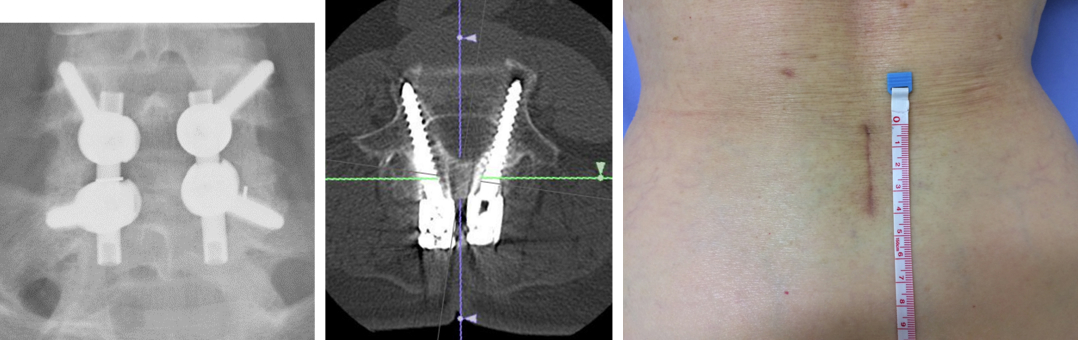

腰椎すべり症など、腰椎の不安定性が問題となる場合には椎体間固定術(PLIF、TLIF)を行います。術前に3次元画像でシミュレーションを行い、詳細に術前計画を立てます。

固定にはスクリューを使用しますが、術野の展開が少ない低侵襲な方法でスクリュー刺入を行います。1椎間の固定であれば4cmほどの傷で手術が可能です(体格にもよります)。

CBT法によるPLIF

筋肉を展開せずに、皮膚の上からスクリューを刺入する方法(経皮的椎弓根スクリュー PPS)を選択する場合もあります。皮膚から突き出たガイドを利用してスクリュー間の連結を行います。筋肉を骨から剥がさずにスクリューを刺入するので、筋肉のダメージが少なくなります。

術 前

2椎間前方固定術後